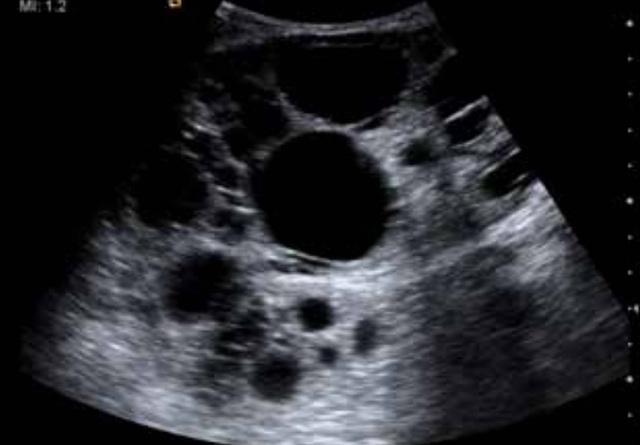

其中一名肾脏移植接受者是一名 24 岁男性坏死性肾小球肾炎终末期患者,其 10 年前曾做过肾移植手术。在移植术后的肾脏超声检查中发现,移植肾发现有两个类圆形囊肿,直径分别为 2.0cm 和 1.0cm。数年后肾脏 B 超检查结果如下。

另一名肾脏移植接受者是一名 57 岁男性,伴有慢性间质性肾炎。在肾脏移植手术中未发现移植肾脏形态的异常,手术超声检查中发现在肾皮质和盂旁均发现类圆形囊肿,直接分别为 1.7cm 和 1.8cm。数年后肾脏检查结果如下。

上述两位肾脏接受者在随后的检查中均发现,肾脏体积增大,其内囊肿体积增大,数量增多,最终病理结果诊断为多囊肾。两个移植的肾脏分别运行了 10 年和 14 年。